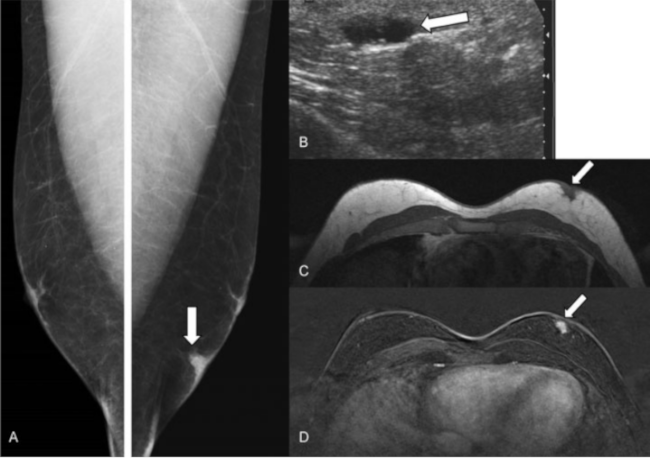

No son precursores obligatoriamente de carcinoma de mama, pero sí son marcadores de riesgo para carcinoma invasor en ambas mamas (algo más en la mama ipsilateral). La hiperplasia lobulillar atípica multiplica por cuatro o cinco el riesgo de desarrollar carcinoma infiltrante, mientras que el carcinoma lobulillar in situ (►Fig. 6) lo hace por 8-10.19

Neoplasia lobulillar in situ. Mujer de 48 años que acudió por masa palpable en mama derecha. (A) Mamografía digital mama derecha. Aumento de densidad de morfología nodular en cuadrantes superiores (delimitado por puntas de flechas amarillas). (B) Ecografía. Nódulo hipoecoico de morfología irregular y bordes mal delimitados (flecha). (C) RM con contraste intravenoso. Se apreció un realce asimétrico, no masa, con distribución focal (flecha). Se realizó BAG con control ecográfico con resultado de neoplasia lobulillar in situ. Al realizar cirugía de la lesión completa, se obtuvo el mismo resultado.